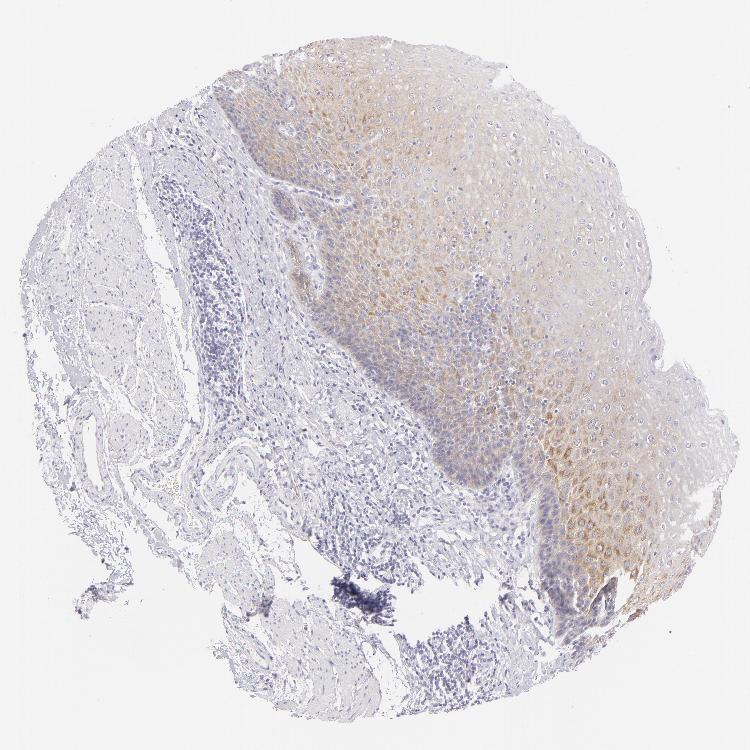

ESOPHAGUS - Antibody stainingi

Antibody staining in the annotated cell types in the current human tissue is reported as not detected, low, medium, or high, based on conventional immunohistochemistry profiling in selected tissues. This score is based on the combination of the staining intensity and fraction of stained cells.

Each image is clickable and will lead to virtual microscopy that enables deeper exploration of all samples and also displays staining intensity scores, fraction scores and subcellular localization as well as patient and tissue information for each sample.

Antibody HPA010122Antibody HPA071006Antibody CAB001999Antibody CAB002000

Squamous epithelial cells MediumNot detectedNot detectedLow